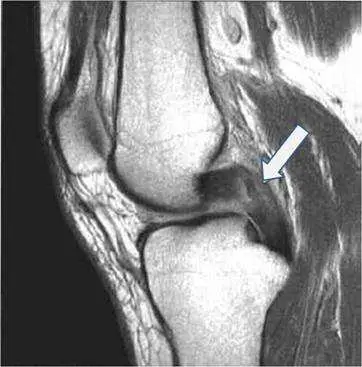

膝關節矢狀面(sagittal plane)磁振造影(MRI)上,後十字韌帶(posterior cruciate ligament, PCL)的正常影像特徵與解剖辨識。

本題影像為膝關節矢狀面 T1 加權 MRI,可清楚呈現膝關節骨性結構(股骨遠端、脛骨近端)及軟組織。白色箭號指向位於後側關節腔內、介於股骨與脛骨之間的一條弧形、均勻低訊號(low signal intensity)帶狀結構,其走向由後下(脛骨後側髁間區)向前上方(股骨內側髁的外側面)延伸,呈現明顯的弧形曲線(arcuate shape)。

此結構在 T1 及 T2 加權影像上均呈均勻低訊號,不具有前十字韌帶(anterior cruciate ligament, ACL)可見的纖維紋路(striations)。其位置在關節腔後方偏中央,整體較 ACL 粗大且走行方向不同。這些特徵均符合正常 PCL 的 MRI 外觀。

前十字韌帶(ACL)在矢狀面上位置較前方,走向由前下至後上,且正常 ACL 在 T2 加權影像常可見纖維紋路,兩者可藉此鑑別。